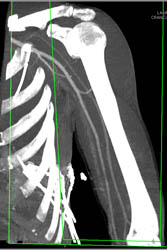

Multiple Hereditary Extosis for Surgical Planning